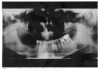

Figure 2 illustrates advanced enamel caries on the mesial surface of the premolar.

Figure 2 - Advanced Enamel Caries

Figure 2